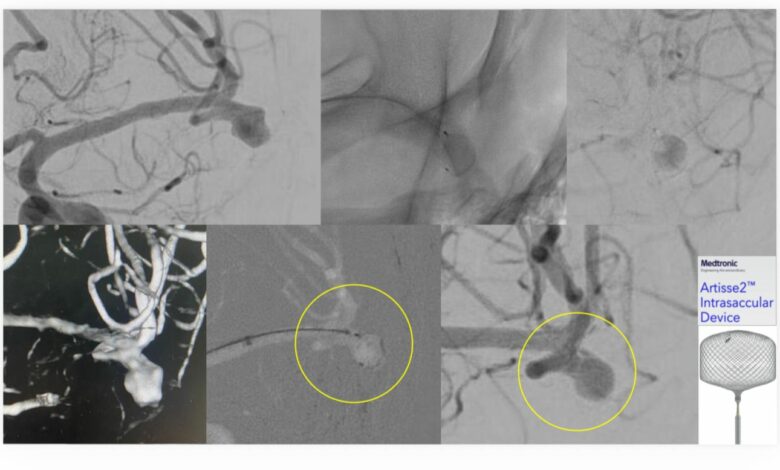

نجح فريق الأشعة العصبية التداخلية في مستشفى الملك فهد الجامعي التابع للمدينة الطبية الأكاديمية بجامعة الإمام عبدالرحمن بن فيصل، في علاج مريض يعاني من تمدد شرياني دماغي واسع العنق، وذلك في أول استخدام سريري لتقنية Artisse™️ في المنطقة الشرقية.

وتمكّن الفريق الطبي من إغلاق التمدد الشرياني بالكامل باستخدام التقنية الحديثة، وخرج المريض من المستشفى وهو بكامل عافيته ، حيث تتميز تقنية Artisse™️ بإمكانية زرع الجهاز داخل التمدد الشرياني بحيث يأخذ شكله بدقة، ما يسهم في تقليل زمن الإجراء وتقليل جرعة الأشعة والصبغة المستخدمة أثناء القسطرة، كما تتيح في كثير من الحالات تجنب استخدام مسيلات الدم بعد الإجراء، الأمر الذي يساعد في تسريع تعافي المريض وعودته إلى حياته اليومية بشكل أسرع.